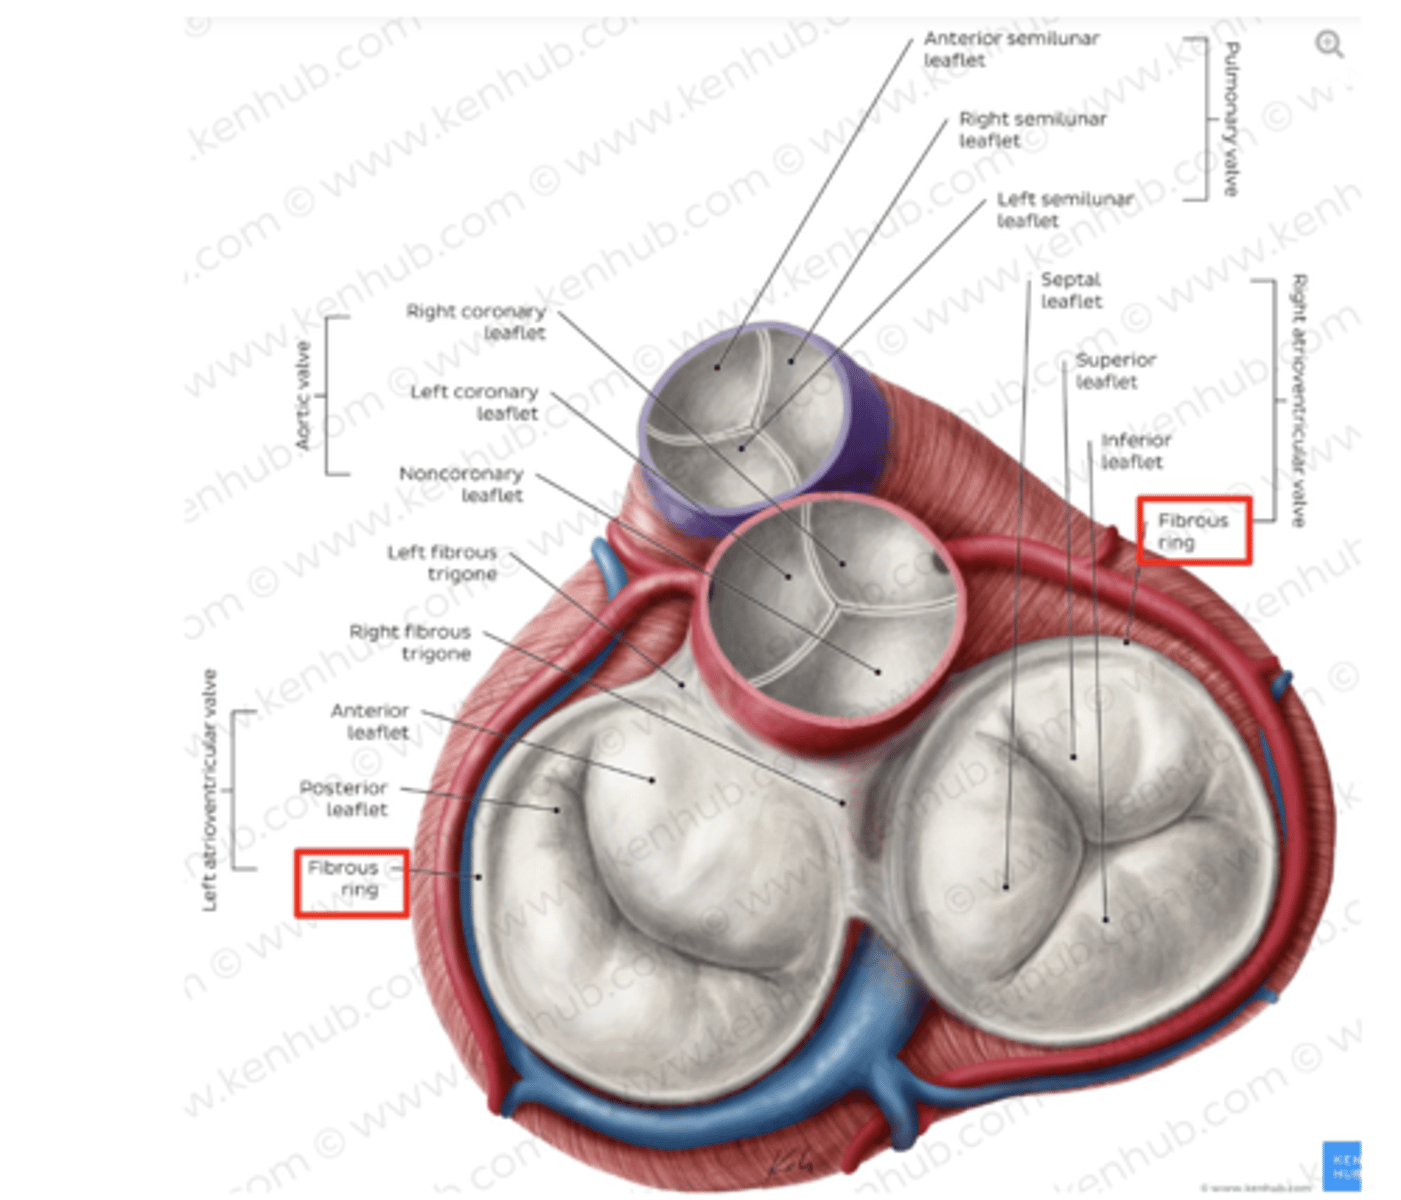

What are the 3 cusps of the tricuspid valve?

Anterior

Posterior

Septal

What are the positions of the pulmonary valve cusps?

Anterior

Right

Left

What are the 3 parts of the pulmonary valve?

. Nodules. (little point at the center)

. Lunules (from the nodule to the wall)

. Sinus (left in between)

What is the valve in the AV left canal?

. Mitral valve

2 cusps (anterior and posterior) and 2 associated papillary muscles

What is the valve to prevents reflux in the aorta?

Aortic valve

What are the 3 parts of the aortic valve?

3 semilunar cusps

posterior

right

left

POSITION IS DIFFERENT THAT IN THE PULMONARY (posterior vs anterior)

What is the structure of the cusps of the aortic valve?

. Nodules

. Lunules

. Small holes for the coronary arteries

MAIN DIFFERENCE WITH PULMONARY VALVES ARE THE SMALL HOLES FOR THE CORONARY ARTERIES.

What are other functions of the rings in the cardiac skeleton?

maintain the shape of the openings between the heart's chambers

insertion site for the cusps of the valves and muscular heart tissue.

What are the components of the cardiac skeleton?

. pulmonary ring,

. aortic ring

. AV rings

RINGS ARE IN THE SAME PLANE AROUND THE VALVES